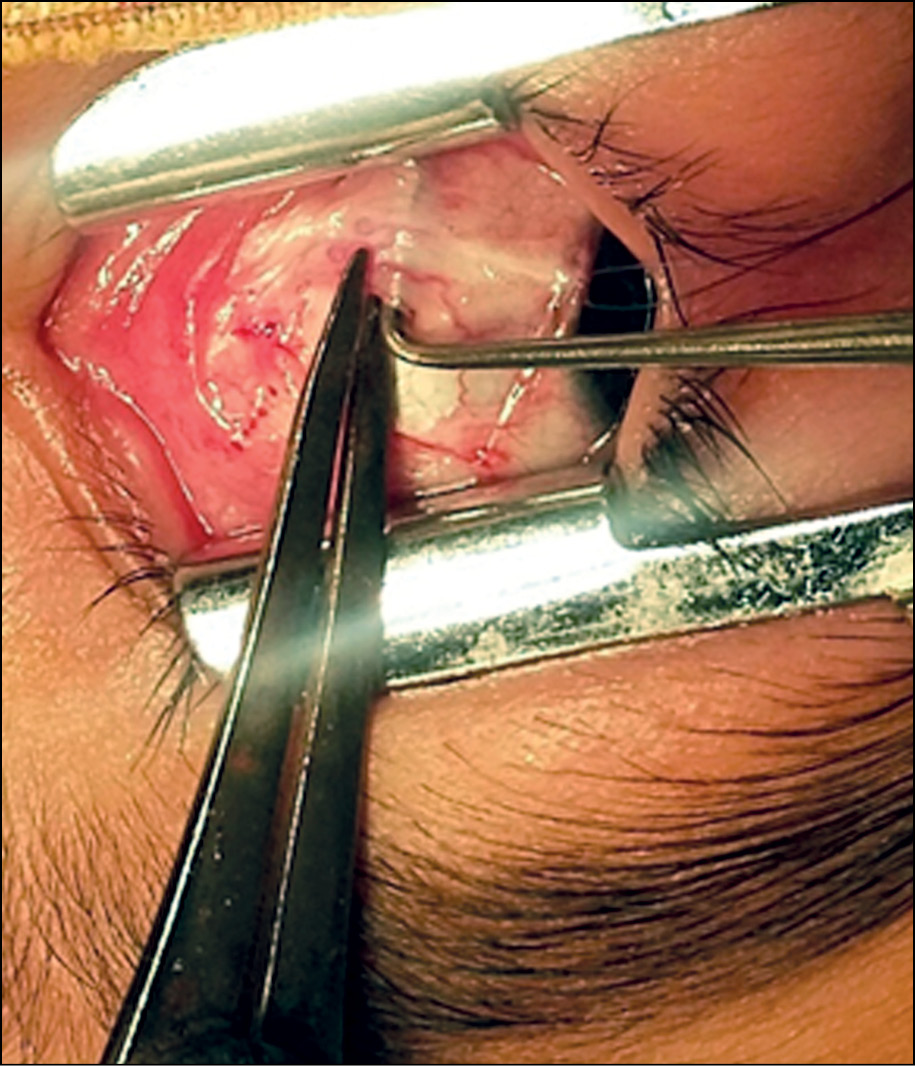

В ходе оперативного вмешательства, после выделения горизонтальных мышц с помощью циркуля Castroviejo измерялось расстояние от места прикрепления верхнего и нижнего края сухожилия до лимба и толщина брюшка без отделения теноновой сумки: при сходящемся косоглазии ВПМ, при расходящемся — НПМ (рис. 2 и 3). При этом старались сильно не тянуть мышцу.

Рис. 2. Измерение места прикрепления сухожилия мышцы – расстояние от лимба.

Рис. 3. Измерение толщины мышцы.